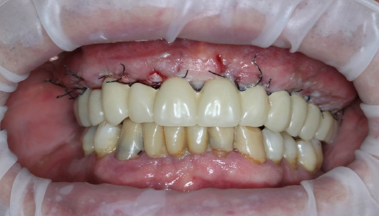

In the resulting post-surgical intermaxillary space, a fixed full-arch temporary prosthesis was digitally designed and manufactured in a complete digital workflow (CAD/CAM) with the occlusal plane parallel to the Camper’s plane and the bipupillary plane, it was then screwed on the implants (Figures 7-12). The definitive prosthesis will be fabricated once the implants are integrated and both hard and soft tissue are healed and stable.

Figure 8A: Maxillary arch immediately after surgery before positioning the temporary full-arch prosthesis.

Figure 8B: Temporary maxillary full-arch prosthesis.

Figure 8C: Temporary maxillary full-arch prosthesis screwed on the implants immediately after surgery.